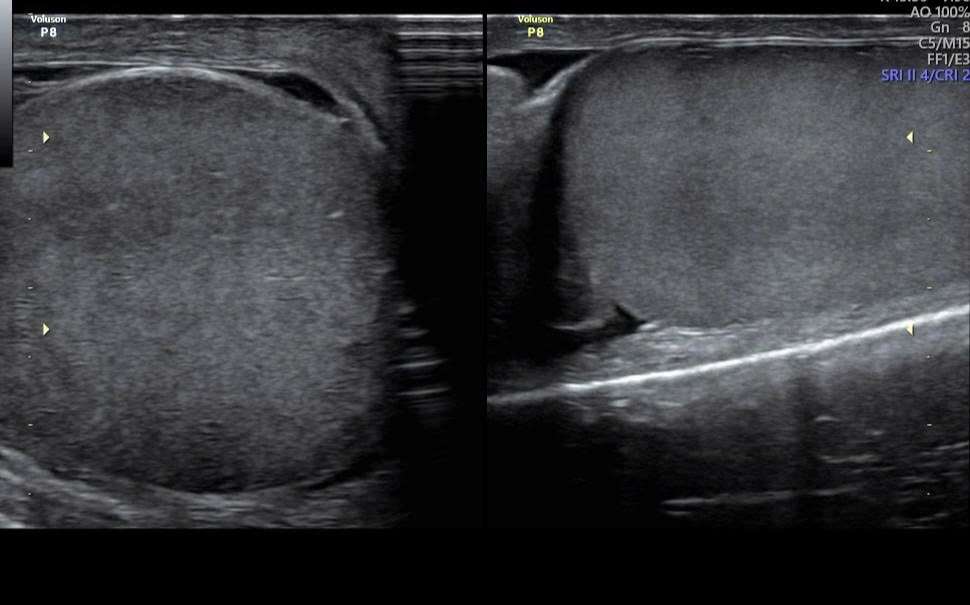

Mình cũng bị giống y chang, không biết nổi từ khi nào, không ngứa, không thấy ảnh hưởng gì, chưa đi khámBạn xem hộ mình như này là bị gì và cần xét nghiệm gì?